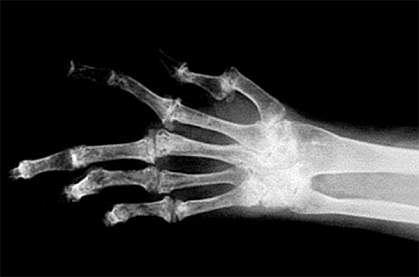

Researchers discovered a third gene that accounts for previously unexplained forms of osteogenesis imperfecta, a genetic condition that weakens bones, results in frequent fractures and is sometimes fatal.

Osteogenesis imperfecta affects between 20,000 and 50,000 Americans. About 85% of all cases are caused by mutations in the genes needed to make the protein collagen. Collagen functions as a molecular scaffolding that holds together bone, skin and other tissues.

The researchers diagnosed a 12-year-old boy and his 4-year-old sister as having a novel form of osteogenesis imperfecta, as described in the online edition of the New England Journal of Medicine on January 20, 2010. The children's parents were immigrants from Senegal living in New York. Although the children's bones were brittle and highly susceptible to fracturing, they did not have shortening of the upper portion of limbs seen in children with mutations in CRTAP and P3H1.